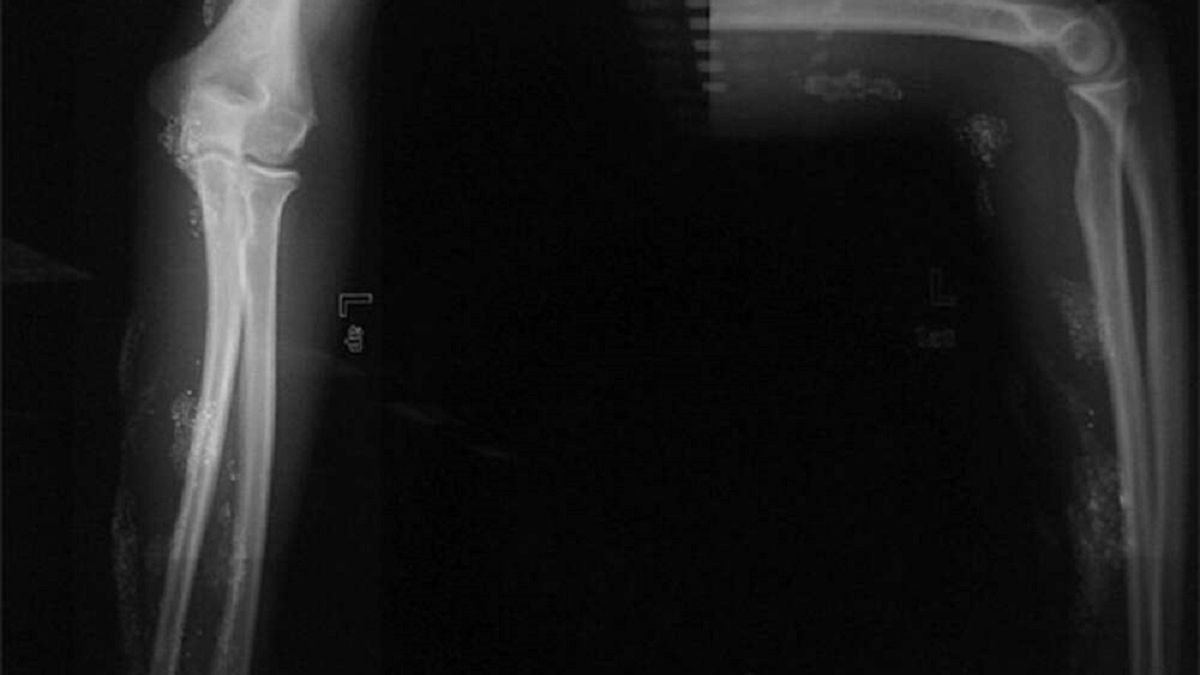

Miał liczne wrzody na przedramieniu

Chłopiec trafił do ośrodka urazowego III stopnia. Miał liczne wrzody na przedramieniu, które nie znikały przez ponad dwa miesiące. W związku z tym, że chłopak nie miał żadnych innych poważnych objawów, lekarze doszli do wniosku, że jego owrzodzenia spowodowane są substancjami odurzającymi.

Lekarze ustalili, że chłopiec próbował rozwinąć swoje supermoce również w inny sposób — pozwolił, aby ugryzł go pająk, licząc na to, że uzyska moce podobne do Spidermana. Testy potwierdziły, że nastolatek miał podwyższony poziom rtęci w moczu. Na szczęście udało mu się wstrzyknąć rtęć tylko pod skórę, a nie do żył, dlatego zrobił sobie mniejszą krzywdę.

Po usunięciu martwej tkanki i rtęci chłopiec mógł opuścić szpital. Lekarze podkreślili, że hospitalizacja chłopca była nietypowym zjawiskiem dla szpitala, ponieważ wszystkie wcześniejsze przypadki celowego wstrzyknięcia rtęci wiązały się z próbą samobójstwa.